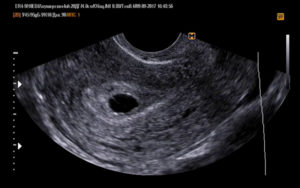

Во время ультразвукового исследования врач может обнаружить замершую беременность. Этот метод считается «золотым» стандартом при диагностике данной патологии. Отсутствие сердцебиений и отставание плода в размерах – главные симптомы замершей беременности при УЗИ.

• УЗИ: покажет прекращение сердцебиения плода. Не паникуйте раньше времени, если врач не услышал сердцебиение плода через стетоскоп — такое возможно при переднем расположении плаценты или наличии жировой прослойки на брюшной стенке;